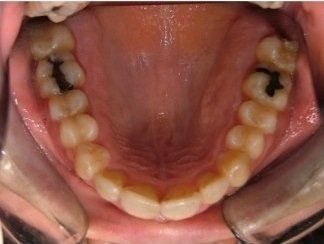

Il trattamento ortodontico non è solo per i bambini: se hai denti storti, affollati, mancanti o prominenti che ti impediscono di masticare e parlare liberamente, potrebbe essere necessario rivolgersi a uno specialista. L’ortodonzia prevede l'uso di apparecchi ortodontici, che possono essere fissi o rimovibili.

I dentisti studiano infatti le anomalie di costituzione, posizione e sviluppo di denti e ossa mascellari, e progettano l’apparecchio mirando al ripristino della corretta funzionalità dell'apparato masticatorio.